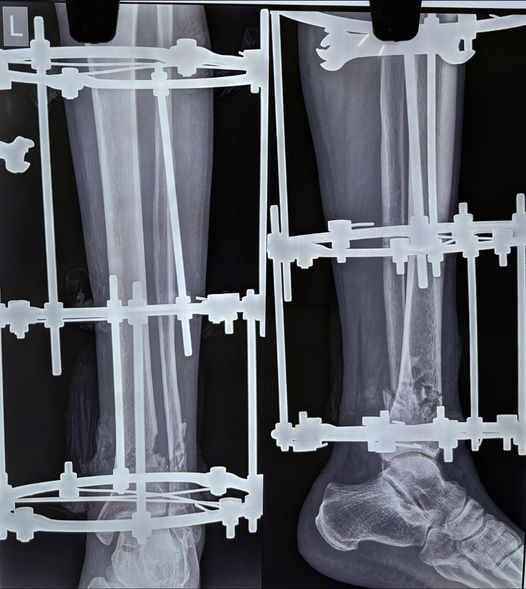

An openfracture is an injury where bones jut out of the limb through a wound, these are often results of high energy road traffic accidents, most surgeons prefer to treat these via multiple surgeries. treating of such fractures in one go is often tricky, as parts of bone and soft tissue and skin goes missing at the site of trauma. In such cases the ilizarov ring fixation system is the magic that helps. This system was developed in russia in the 1950s in the heights of cold war era. I guess this will always be a prime example of “necessity is the mother of invention”